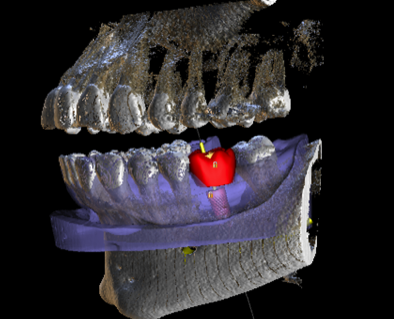

2. Virtual implant placement

Supply us with the implant brand and size and we will position it exactly to your specifications and in relation to the virtual final tooth position. We will send a written report for you to check and note any changes if needed. We will not make the guide until you are 100% satisfied with the virtual placement. Alternatively use free software to plan the case yourself and send us the plan file and we can make the guide from that.

3. Approval of implant report

Approve the plan so construction of the implant guide can go ahead, this must be done via replying to our email. Let us know what type of guide you wish to select and what size of drills you will be using. See next point for more information on types of guides.

Various types of guides are available for you to select. All can be tooth borne, tissue borne bone supported* or a combination of each. * Bone supported guides are dependant on CBCT quality.